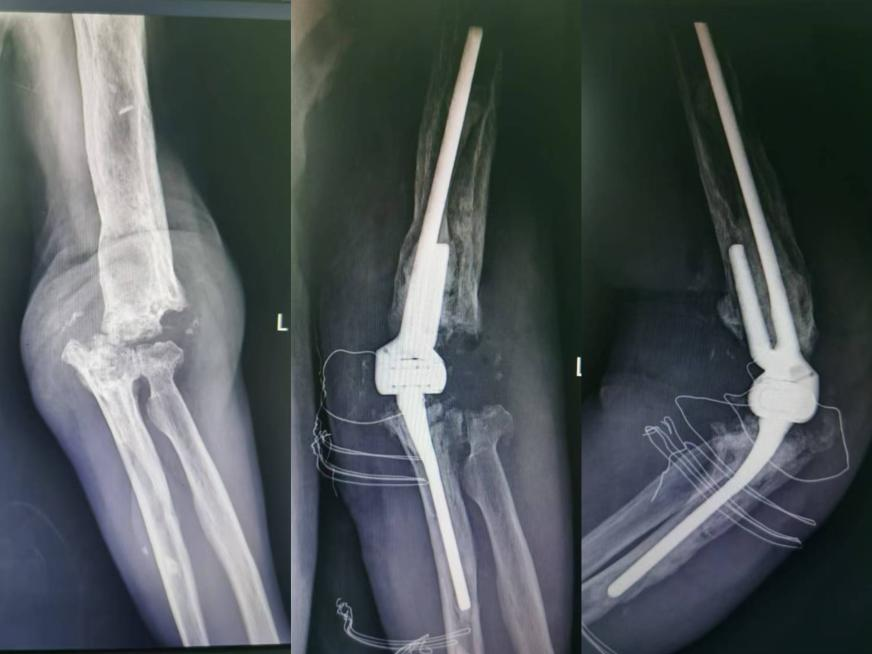

郝姓老人,68岁,20多年前因为车祸导致左侧肘关节粉碎性骨折,做了左侧肘关节置换手术。1年前,老人肘关节肿胀、流脓,肘关节活动明显受限,诊断为肘关节假体周围感染,在我院关节外科行假体取出旷置术,并在关节外科进行了全流程管理,最终感染得以控制。今年6月份,老人再次来到我院关节外科,要求重建左侧肘关节。考虑到患者既往感染史,肘关节周围骨缺损较大,周围软组织状态差,血管神经走行变异,手术难度极大,在王坤正教授的指挥下,我院关节外科主任杨佩教授为老人定制了专用假体,并在王春生副教授、田润副主任、孔宁医生的协助下,造成了肘关节再置换术。术后老人恢复良好,按时出院。